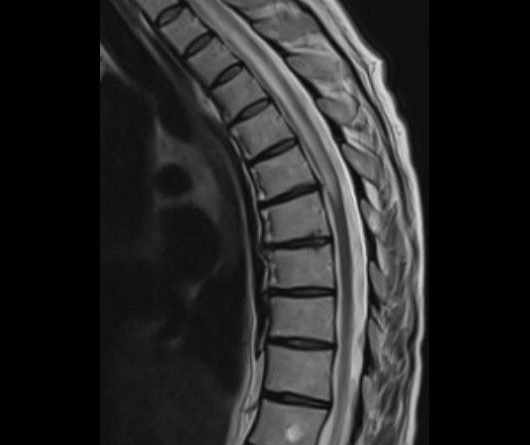

- (A) Torakal MRG’de sagital görüntülerde üst-orta torakal düzeyde T2A hiperintens (oklar), T1A izo-hipointens (ok) uzun segment ekspansil sinyal değişikliği izlenmekte olup sagital postkontrast T1A’da kontrast tutulumu mevcuttur (oklar). Bulgular longitudinal ekstensif transvers miyelit (LETM) ile uyumludur.

- Transvers miyelit sıklıkla santral gri cevheri etkileyen ve üç veya daha fazla vertebral gövde uzunluğunu etkilemektedir (LETM).

- Olgularının %15’i MS’e benzer şekilde kısa transvers miyelit ile karşımıza çıkabilir.

- Transvers kesitlerde, santral kordu tutma eğilimindedir.

- Omurilik atrofisi ve ekspansiyon/ödem MS’e göre daha fazla görülür.

- Kontrast madde enjeksiyonu sonrasında neredeyse tüm akut NMO lezyonları, yamalı, düzensiz veya periferik olarak kontrastlanma gösterir.